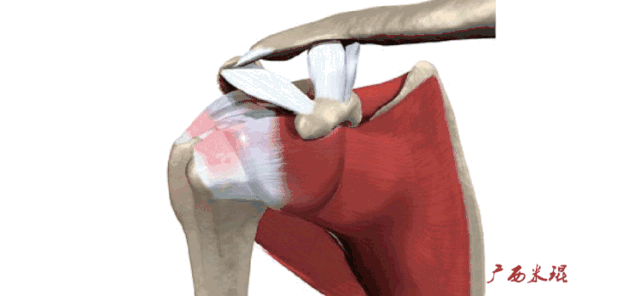

肩袖(Rotator cuff)损伤由Smith于1834年发现并命名,指组成肩袖的冈上肌、冈下肌、肩胛下肌和小圆肌的损伤。肩袖是以上4条肌腱共同组成的功能复合体,呈一个袖套状包绕肱骨头,维持盂肱关节的稳定,同时提供肩关节活动时所需的动力。

冈上肌主要功能是肩关节外展,当然外展功能还需要三角肌等协助。

冈下肌和小圆肌的主要功能是肩关节外旋,肩胛下肌的主要功能则是肩关节内旋,旋转袖由此而来。冈上肌、冈下肌、肩胛下肌或小圆肌的断裂会导致其相应功能的受损。

肩袖损伤90%发生在冈上肌,然后波及冈下肌及/或肩胛下肌,极少情况下会损伤小圆肌。肩胛下肌由于喙突的撞击可以单独损伤,冈下肌及小圆肌很少单独损伤。MRI阅片中必须抓住这些特点才能够提高诊断的准确率。